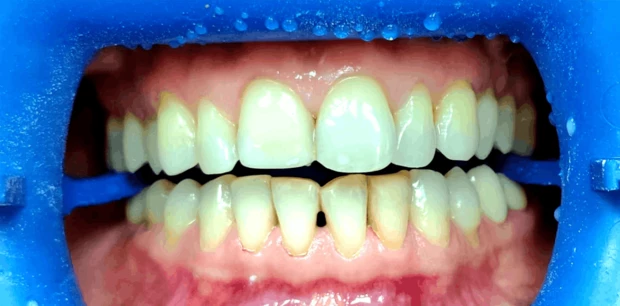

Профгигиена

Профессиональная гигиена зубов

Пациент Ф., 27 лет обратился с жалобами на периодическую кровоточивость десен при чистке зубов и на скученность зубов. Проведена профессиональная гигиена полости рта, пациент направлен на ортодонтическое лечение.